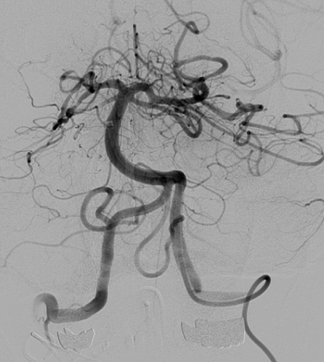

Rekanalisation eines akuten Verschlusses der Arteria Basilaris

Ein akuter Schlaganfall ist zu 80% durch den Verschluß eines hirnversorgenden Blutgefäßes bedingt. Bei entsprechender Klinik des Patienten und nachgewiesenem Gefäßverschluss kann eine katheterbasierte Gerinnselentfernung erfolgen. Das Procedere hierbei ist ähnlich dem einer diagnostischen Angiographie. Das Blutgerinnsel wird mittels eines feinen Drahtgeflechtes aus der Hirnschlagader geborgen. Der Eingriff wird entweder unter leichter Betäubung oder unter Vollnarkose durchgeführt.

Im Klinikum Bemen-Mitte ist die größte Stroke Unit Deutschlands und eine der größten Europas stationiert. Jährlich werden 2500 Schlaganfall Patienten behandelt. Ungefähr 200 von den Patienten haben einen schweren Schlaganfall, der durch einen großen Gefässverschluss verursacht wird. Bei diesen Patienten kann eine Kahteterbasierte Therapie eingestzt werden. Im Jahr 2014 sind 160 Patienten mittels Thrombektomie behandelt worden.